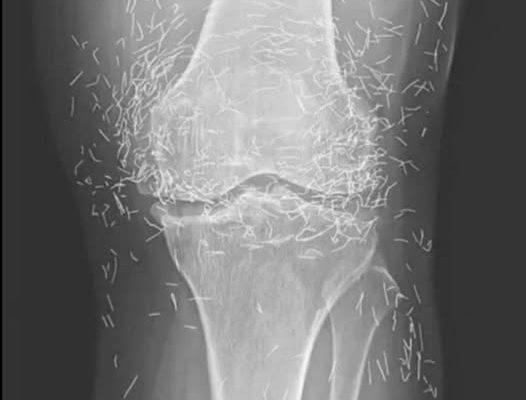

Years later, when doctors took X-rays to evaluate her knee condition, they weren’t prepared for what appeared on the images. Her knees were filled with dozens of bright, metallic flecks — tiny needles embedded deep within the joint area.

The findings were later documented in a case published by the New England Journal of Medicine.